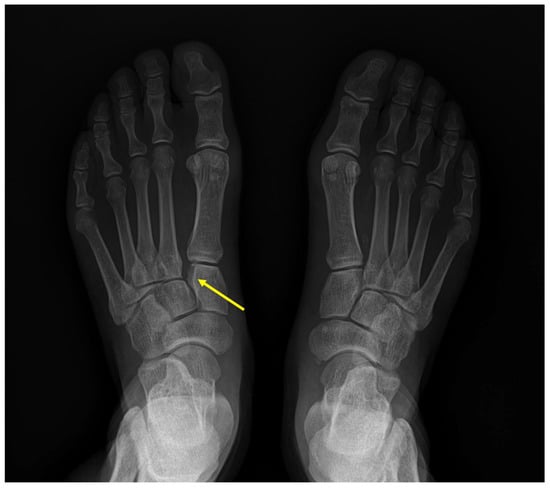

| C1–M2 | Medial cuneiform—second metatarsal bone damage with diastasis |

| C1–C2 | Medial cuneiform—intermediate cuneiform instability |

| C1–M1 | Medial cuneiform—first metatarsal bone instability |

| C2–M2 | Intermediate cuneiform—second metatarsal bone instability |